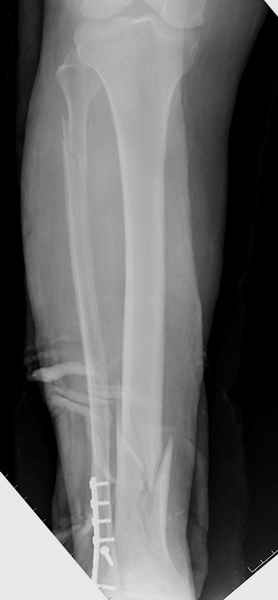

спрашивает что делать с больным который поступил недавно, фермер 55 лет падение при пьяной драке в баре, года два назад перенес операцию на лодыжке, на снимках и КТ перелом без вовлечения сустава,

Здесь мы использовали новый Synthes Nail с дополнительными дырками, в проксимальной части 4: по две косых и поперечные (один стандартный а другой динамический), в дистальной части две поперечные, прямая и косая. Вес больного более 120 кг, нагрузку начнем через месяц.

Получилось красиво, поздравляю. Вверху можно было ограничиться одним винтом во фронтальное статическое отверстие, зачем два 45-градусных?

При такий спирали задний край tibia может быть сломан - нет ли этого в данном случае? На всякий случай можно было ввести 1-2 винта 4,5 мм спереди назад мимо гвоздя. Хотя самый дистальный блокирующий винт, возможно, зацепил этот отломок. А какой тут диаметр гвоздя и locking винтов?